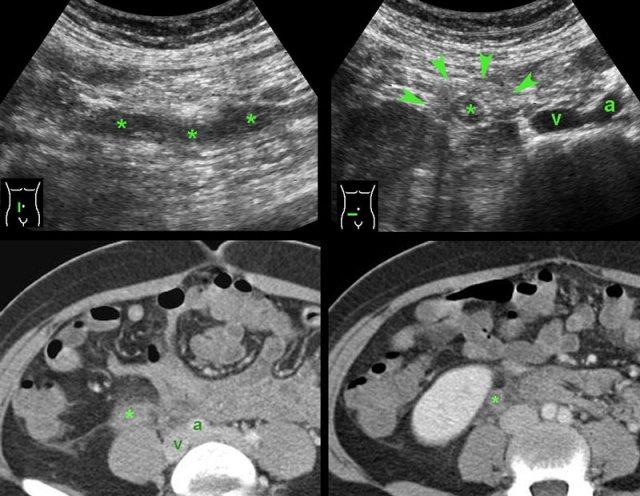

PID giai đoạn sớm với ruột thừa dày thứ phát. (ut. = tử cung, b = ruột non, a và v = động mạch và tĩnh mạch chậu, s = đại tràng sigma)

PID ca lâm sàng 5

Phụ nữ trẻ nhập viện với đau hố chậu phải và CRP 70, nghi ngờ viêm ruột thừa.

Siêu âm cho thấy dịch đục trong túi cùng Douglas (*).

Tại vị trí đau tối đa, quan sát thấy ruột thừa có thể ép xẹp (mũi tên), được bao quanh bởi một ít mỡ tăng âm.

TVUS cho thấy dịch tự do đục, với CRP cao, nhiều khả năng là mủ.

Buồng trứng có hình ảnh bình thường nhưng được bao quanh bởi mỡ tăng âm, đang viêm.

Chẩn đoán:

PID giai đoạn sớm với phản ứng thứ phát tối thiểu của phúc mạc và ruột thừa.

Một ngày sau, PCR Chlamydia cho kết quả dương tính.